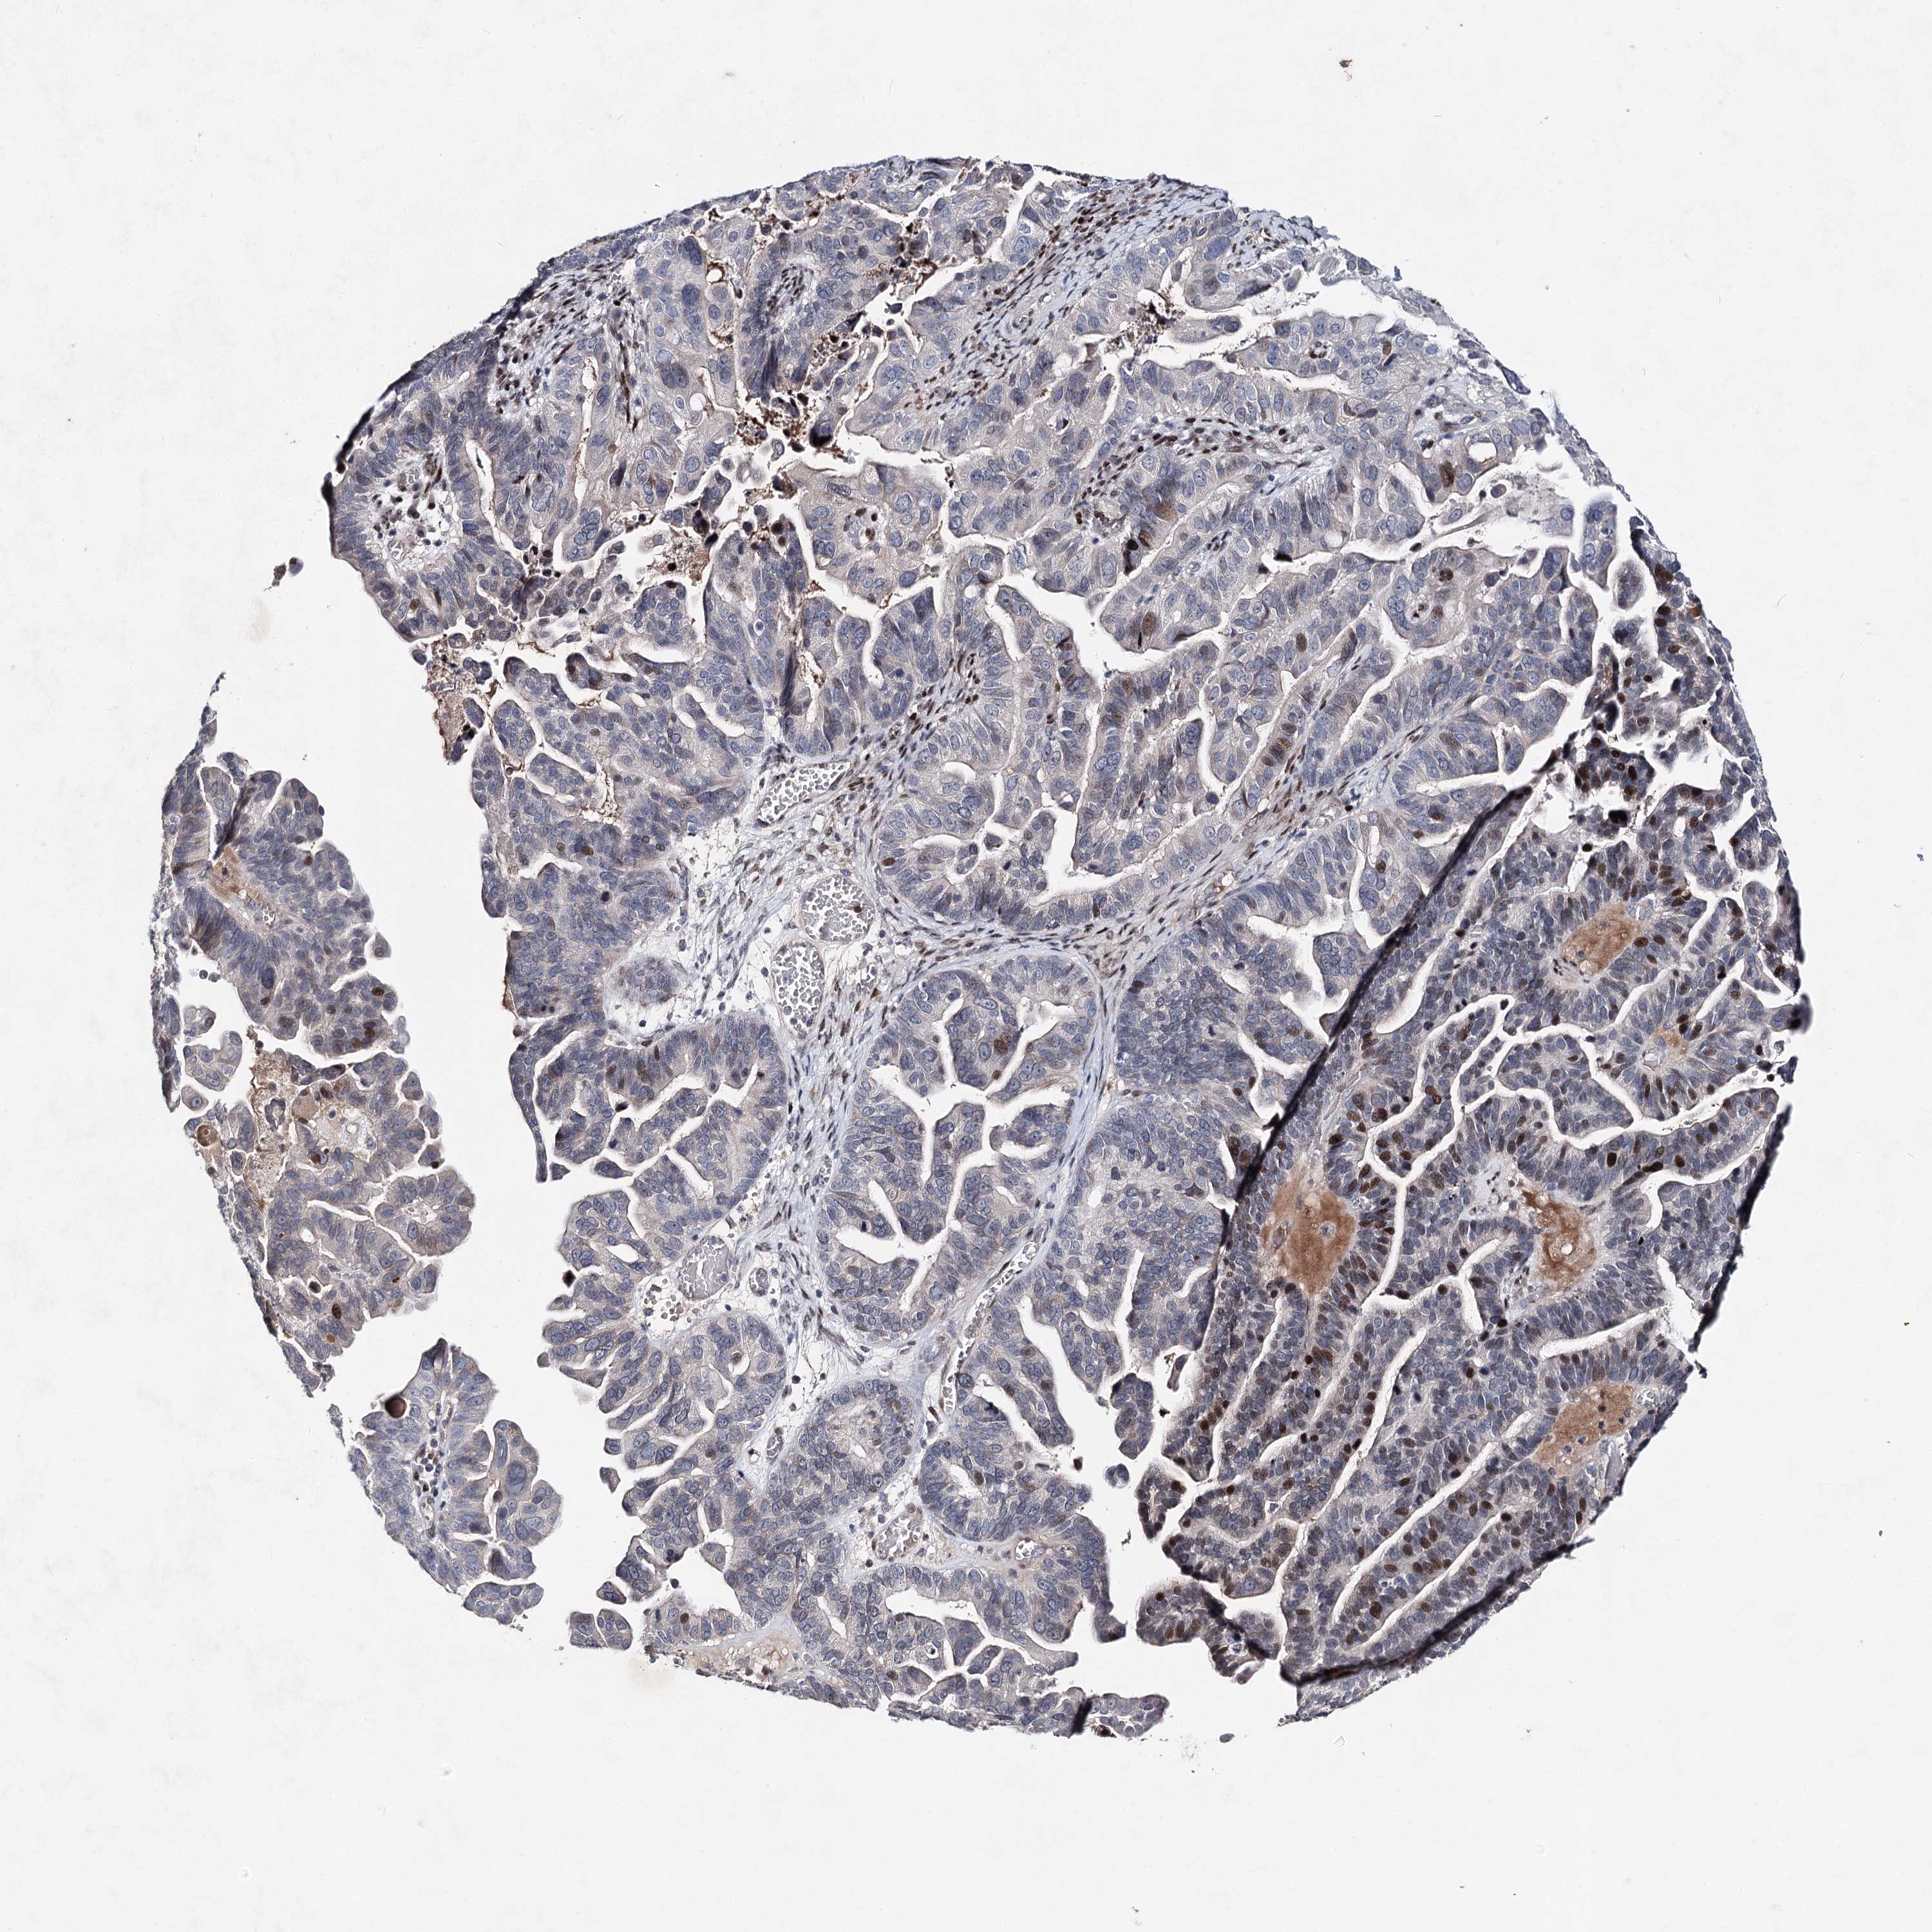

OVARIAN CANCER - Protein expressioni

A mouse-over function shows sample information and annotation data. Click on an image to view it in a full screen mode. Samples can be filtered based on level of antibody staining by selecting one or several of the following categories: high, medium, low and not detected. The assay and annotation is described here.

Note that samples used for immunohistochemistry by the Human Protein Atlas do not correspond to samples in the TCGA dataset.

Antibody stainingi

Antibody staining in the annotated cell types in the current human tissue is reported as not detected, low, medium, or high, based on conventional immunohistochemistry profiling in selected tissues. This score is based on the combination of the staining intensity and fraction of stained cells.

Each image is clickable and will lead to virtual microscopy that enables deeper exploration of all samples and also displays staining intensity scores, fraction scores and subcellular localization as well as patient and tissue information for each sample.

Antibody HPA038449

Staining

High

Medium

Low

Not detected

Intensity

Strong

Moderate

Weak

Negative

Quantity

>75%

75%-25%

<25%

None

Location

Nuclear

Cytoplasmic/membranous

Cytoplasmic/membranous,nuclear

Cystadenocarcinoma, serous, NOS

Carcinoma, endometroid

Cystadenocarcinoma, mucinous, NOS

Carcinoma, NOS